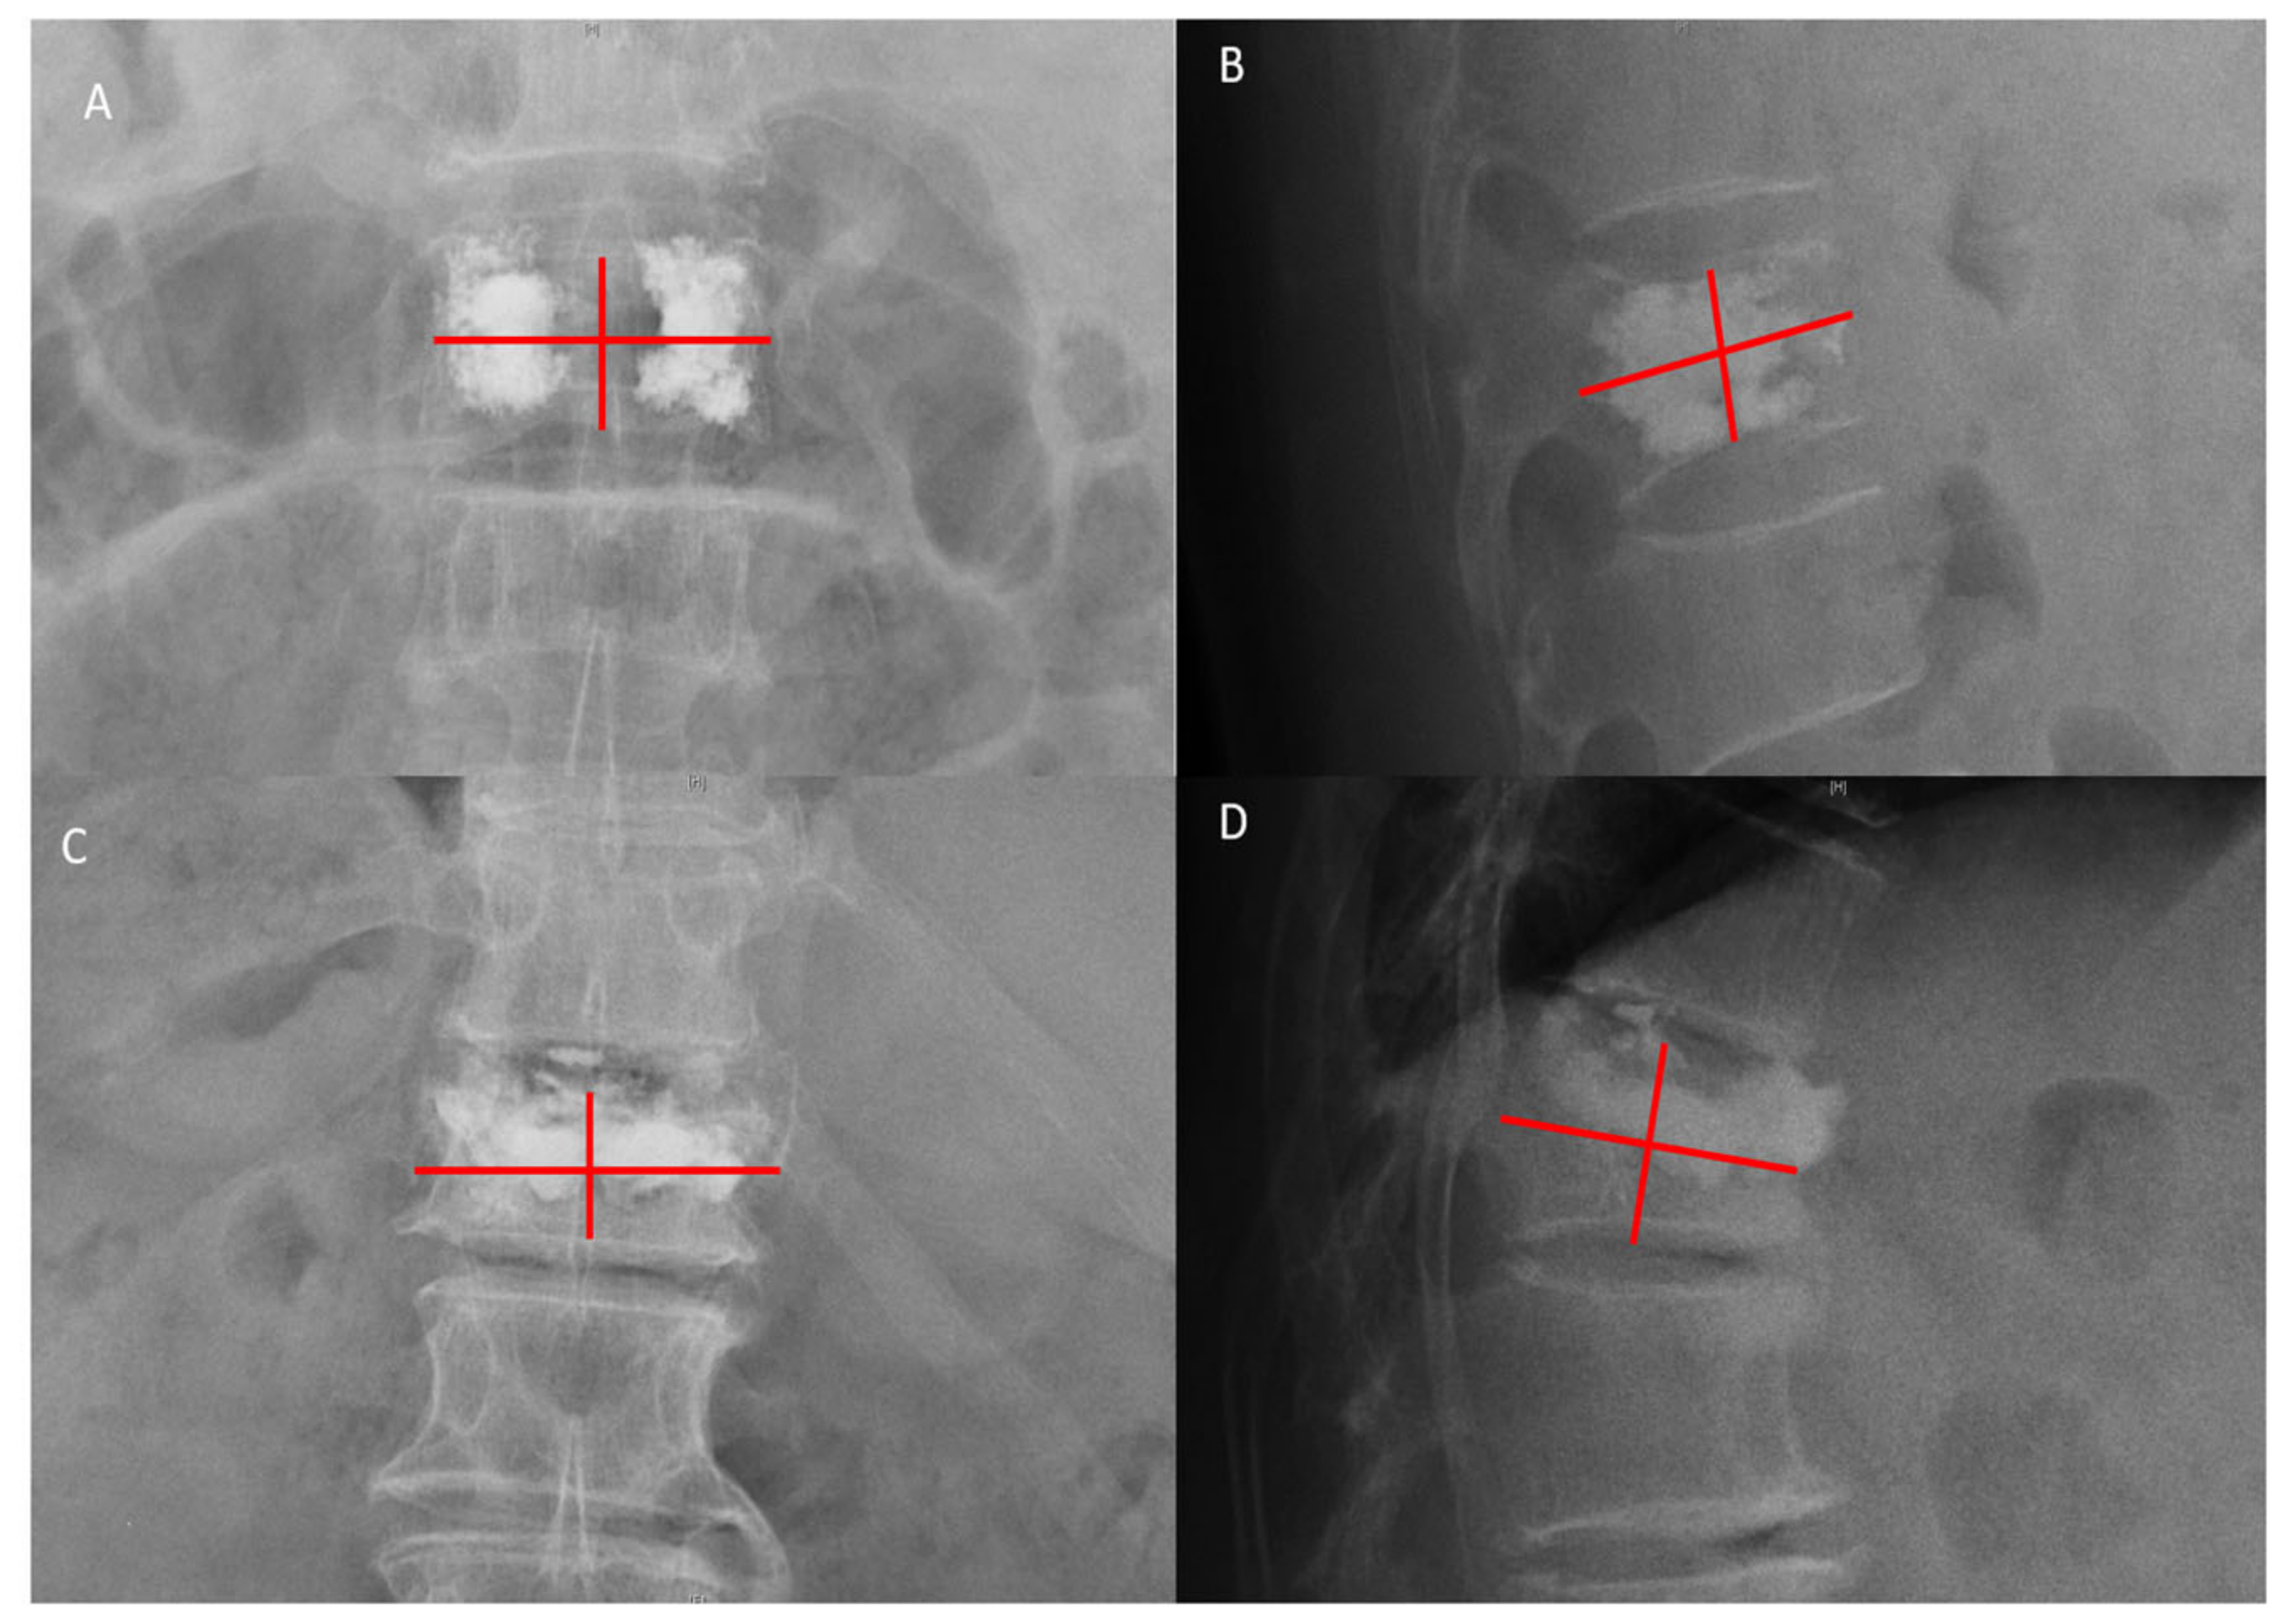

| Cement leakage | <0.001 | 0.002 | <0.001 | 0.588 | |||

| No leakage (n, %) | 8 (38.1) | 9 (25.7) | 571 (68.0) | ||||

| Anterior leakage (n, %) | 11 (52.4) | 23 (65.7) | 157 (18.7) | ||||

| Others (n, %) | 2 (9.5) | 3 (8.6) | 112 (13.3) | ||||

| Bone cement distribution score | 7.73 ± 1.88 | 7.85 ± 1.76 | 8.08 ± 1.43 | <0.001 | 0.007 | 0.042 | 0.824 |